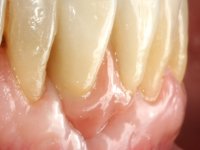

Splinting of teeth 41 and 31 to the adjacente teeth with a metallic mesh allowed us to temporarily resolve the esthetic situation and simultaneously avoid the use of a removable prosthesis, during the healing of the sockets and also during the osteo-integration phase of the dental implant.